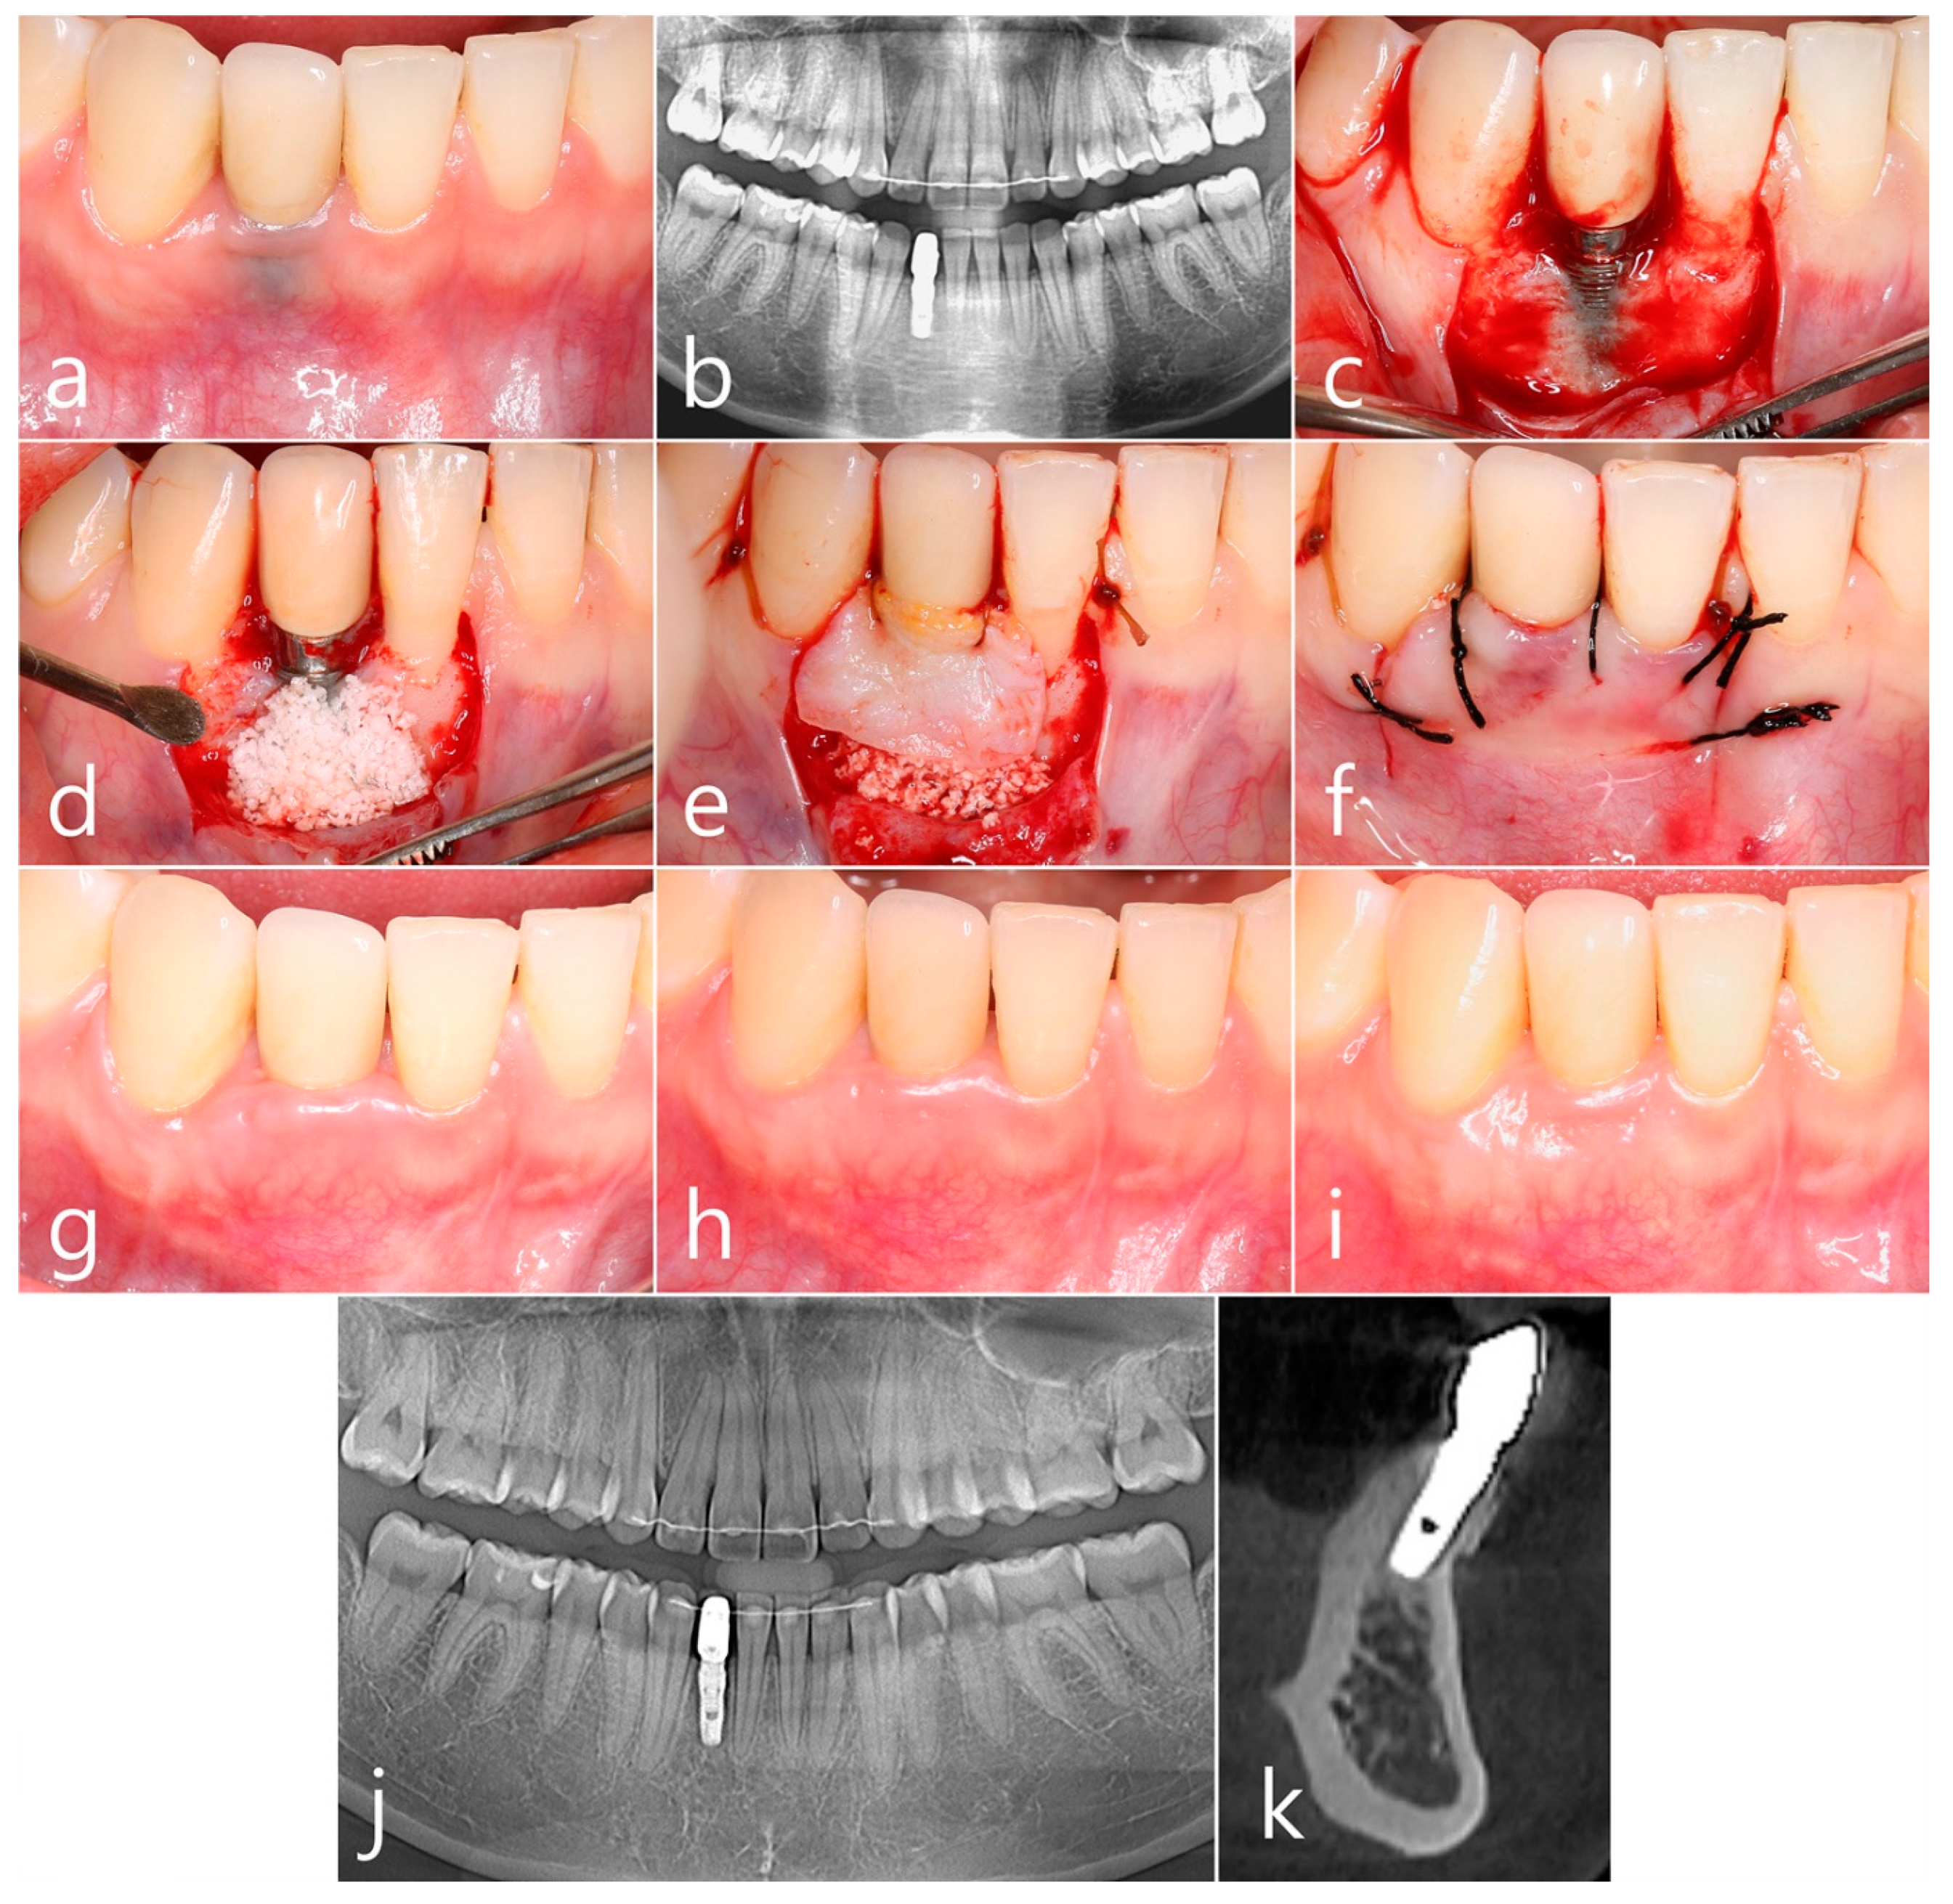

2.1. Case 1